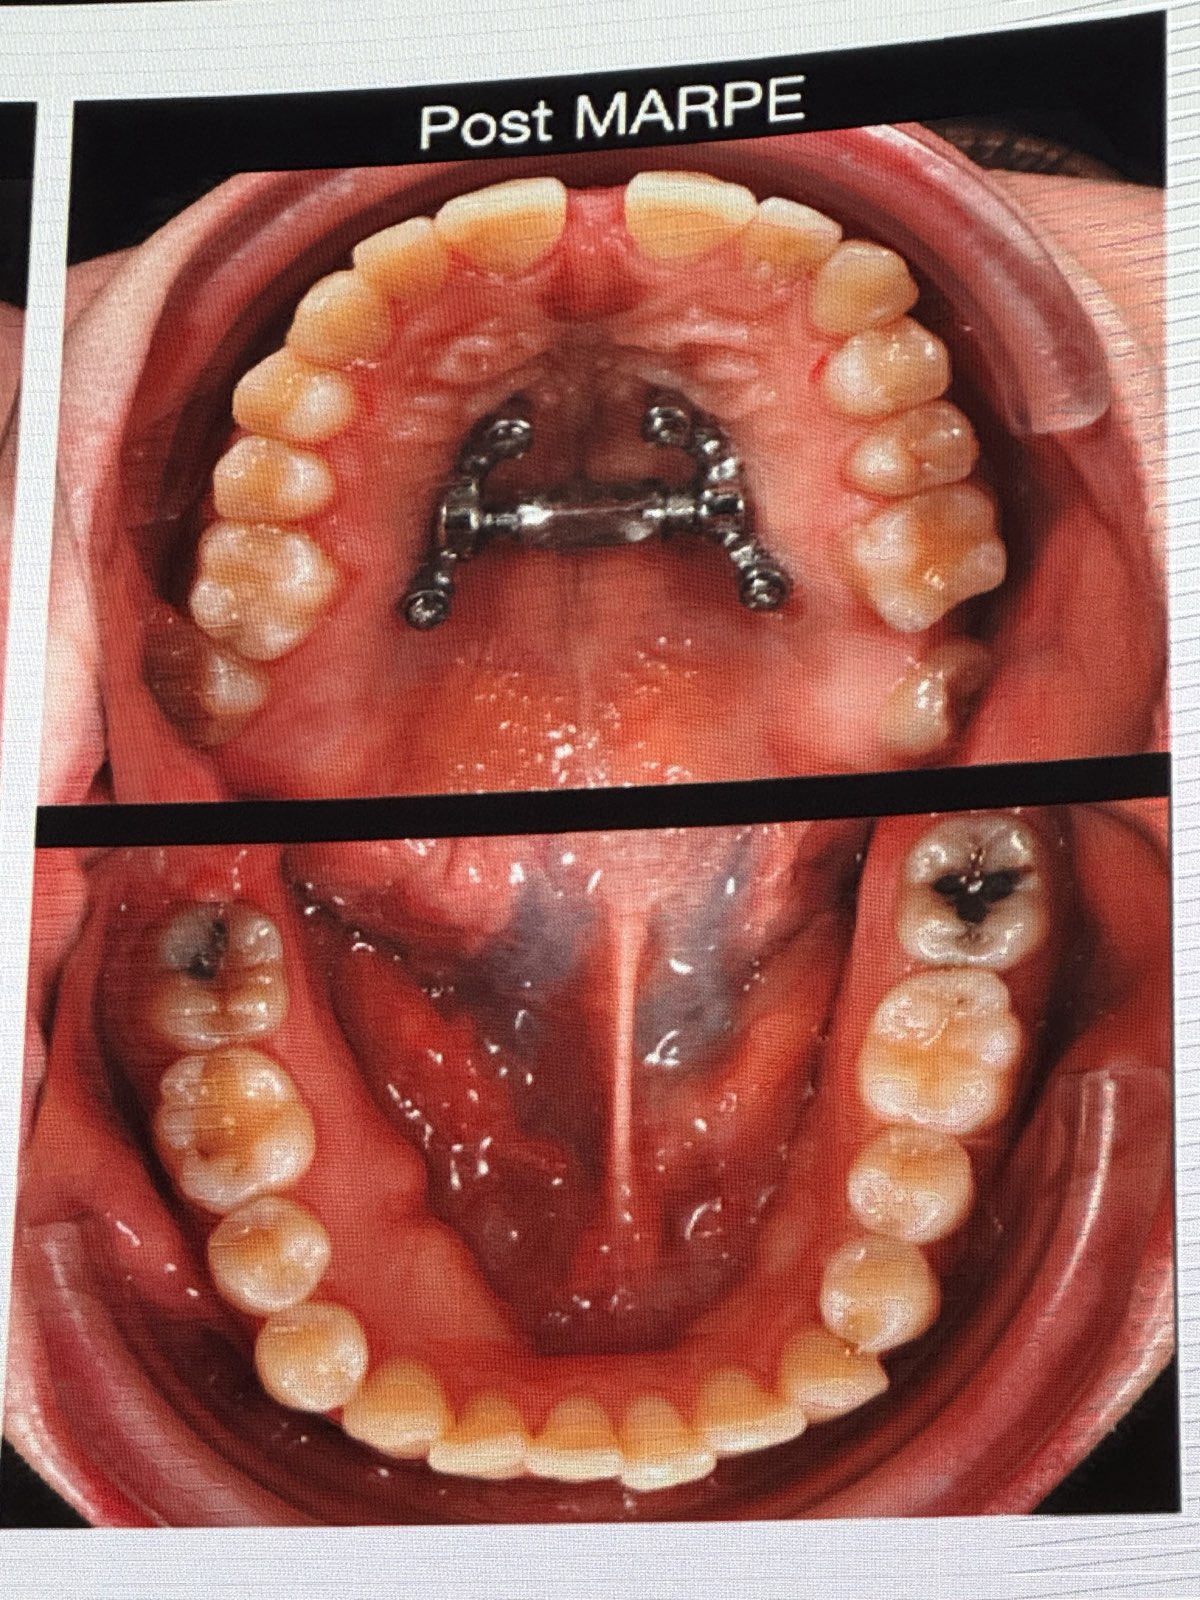

• MARPE(上顎急速拡大装置)に関する言及

• 重度横幅狭窄のある成人患者には、パワーネジ(Power Screw, ドイツTiger社製)のような強力なスクリューと、必要に応じて骨切り手術(ピエゾサージェリーシステムによる単純な手術)を併用したMARPEを適用する。

• 骨切り手術: 口蓋側のmaxillaに2つの小さな切開を入れ、ピエゾサージェリーの角度付きチップで縫合線を破断。切歯間にも切開を入れる。

• 効果: MARPEは骨格性の拡大を可能にし、歯の傾斜を防ぎ、成人における難症例の拡大をより予測可能にする。

• Tippingの制御: アライナーのずれを防ぐため、長方形の水平アタッチメントを配置することが有効。